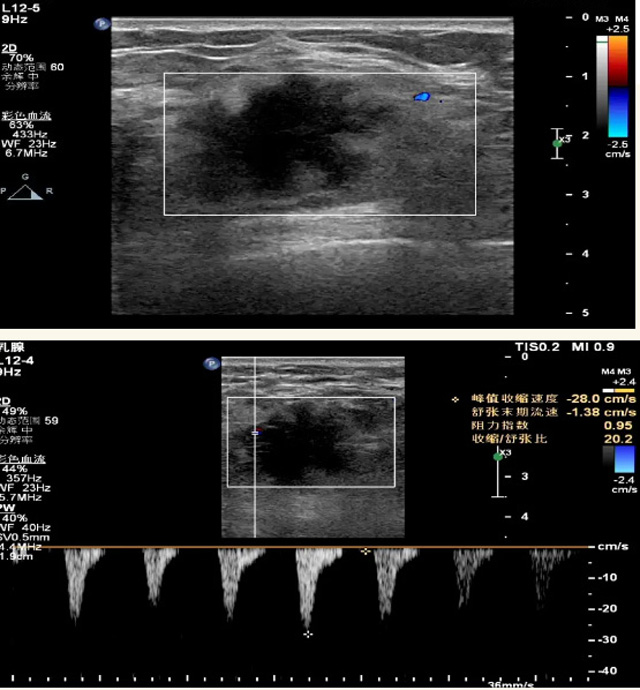

乳腺B超检查无辐射,对囊性病变敏感,可以实时观察病灶。超声引导活检跟手术前的定位。就是它对于微小的钙化查出率比钼靶稍微差点。磁共振MRI检查也是是没有辐射的,对备孕跟已经怀孕的人士比较友好。不用担心这个辐射影响胎儿问题。对乳腺病灶敏感性较高,致密乳腺病灶、乳腺癌的复发,准确鉴别囊性及实性病变。可以帮助临床医生判断恶性、良性病变。但是MRI磁共振对微小钙化不明显,微钙化还是钼靶靠谱点。检查时间比较长,有伪影的影响。费用相对B超,钼靶高很多。